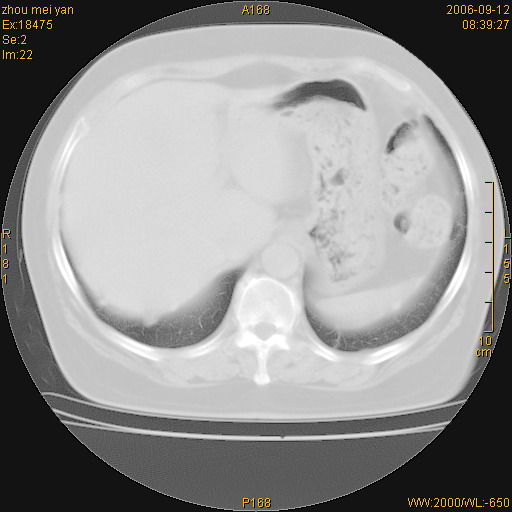

患者、女、55岁。因心率失常住院检查ct发现胸部多发结节。腹部b超肝、胆、胰、脾、肾、子宫附件未见异常。无结核病史,无粉尘接触史。请大家来会诊。谢谢!

病变位于胸膜,多发结节,边界清楚,内见小结节状钙化。其它未见异常。

双侧胸膜多发结节,形态不规则,边缘较清楚,每一个结节中心似乎都有钙化点的特征,与胸膜广基相切。临床无结核病史,无粉尘接触史。

影像表现十分有特点:双侧肋胸膜及膈胸膜广泛散在分布大小在2至6mm左右,较大病灶中心可见钙化。

感染性肉芽肿,双侧膈底胸膜见多个结节灶,内见斑点状钙化,有否疫水接触史

双侧肋胸膜及膈胸膜广泛散在分布大小不等结节影,较大病灶中心可见钙化。